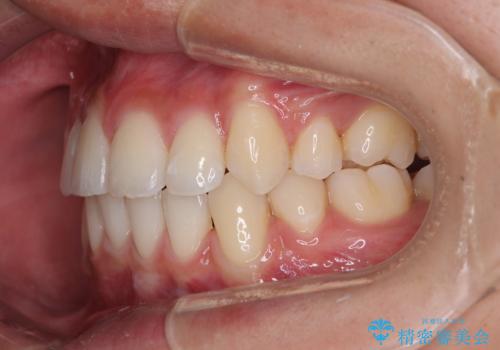

- 八重歯と口元の閉じにくさを気にして来院された患者様です。

非抜歯矯正で歯列を整えると、治療後に口元が今よりも突出する可能性が高かったため、上下左右の第一小臼歯4本を抜歯し、ワイヤー装置にて矯正治療を行うこととしました。

患者様の望んでいた通りの歯列や口元に仕上げることができました。